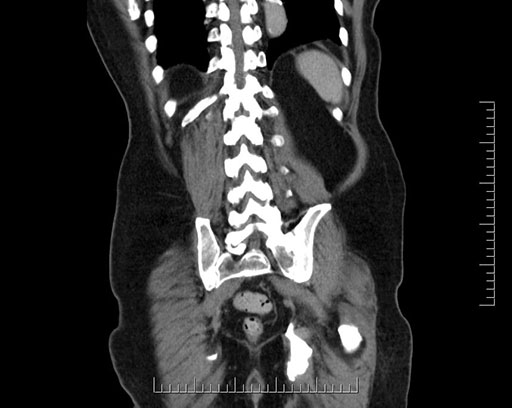

Imaging Analysis

Look through the patient's CT scan to identify any areas of concern for the necessary procedure.

Based on your CT findings, which issue(s) would give reason for "planned slowing down moment(s)" in this case?

Considering a standard Whipple procedure, what step(s) of the operation would you do differently in this case?